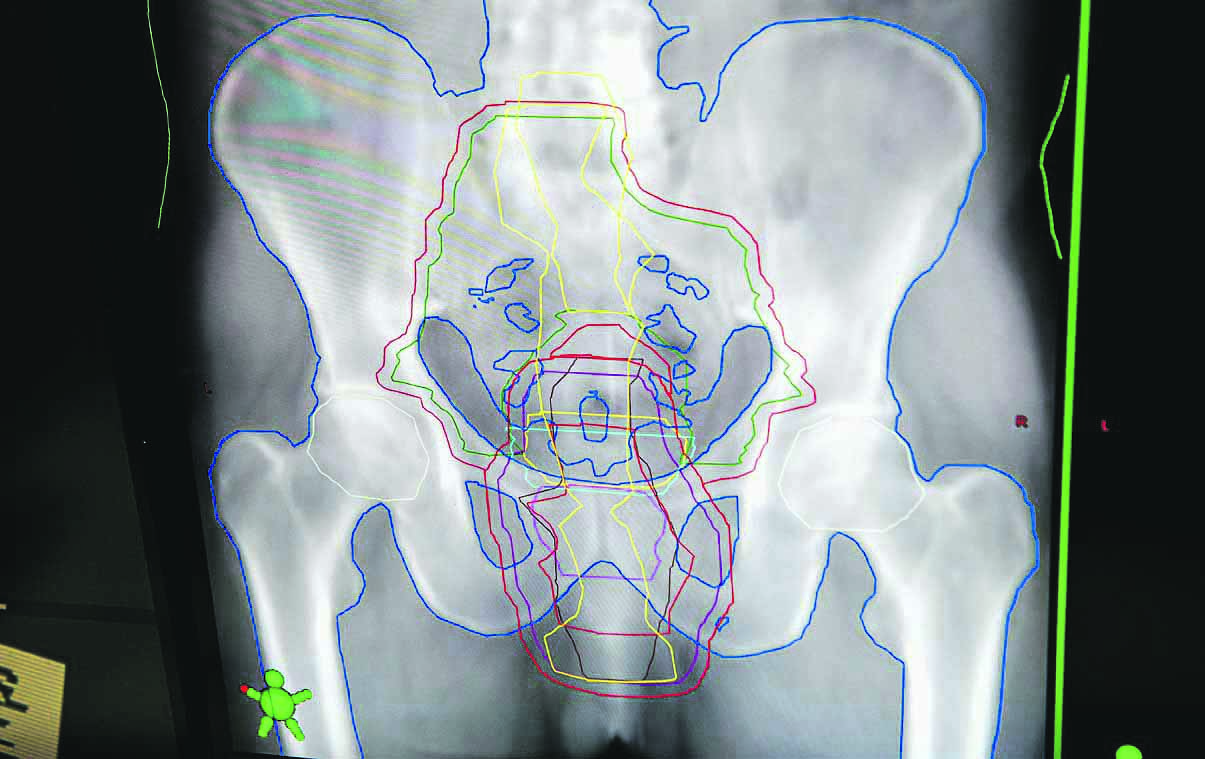

Когда она начинала работать, были старые аппараты, конвенциональная лучевая терапия. Компьютерных томографов не было — только рентгеновские снимки. По ним радиологи рисовали срезы человека, проекцию органов, место, где примерно находится опухоль, а потом по программе рассчитывали, как должно идти облучение.

— Радиотерапия — это достаточно творческая профессия. Работать очень интересно! Ты погружаешься полностью внутрь человека, думаешь, как провести лечение, чтобы максимально облучить опухоль, но при этом не затронуть здоровые органы. Надо знать прекрасно не только анатомию человека, но и физику, математику, геометрию, иметь навыки рисования. Все эти дисциплины я любила в школе, поэтому для меня это интересно. По крайней мере, до сегодняшнего дня я не разочаровалась в своей профессии, — улыбается доктор.

— Планирование лучевой те рапии — сложный и трудоемкий процесс. Вначале проводим подготовку, — расписала алгоритм действий Наталья Сергеевна. — Врач в специальной программе на компьютере рисует опухоль, определяет целевую дозу для этой опухоли и допустимые дозы для окружающих органов, ставит задачу для медицинского физика. Он уже в своей программе создает трехмерный план облучения, рассчитывает, как лучше направить луч и какой силы должно быть его воздействие, пишет программу для аппаратуры. И «умная» машина сама создаёт конфигурацию лучевых лепестков, которые каждую секунду меняют своё положение. А медицинская сестра уже контролирует работу аппарата и положение пациента, чтобы он правильно лежал, все метки совпадали. Такое вот командное лучевое трио.